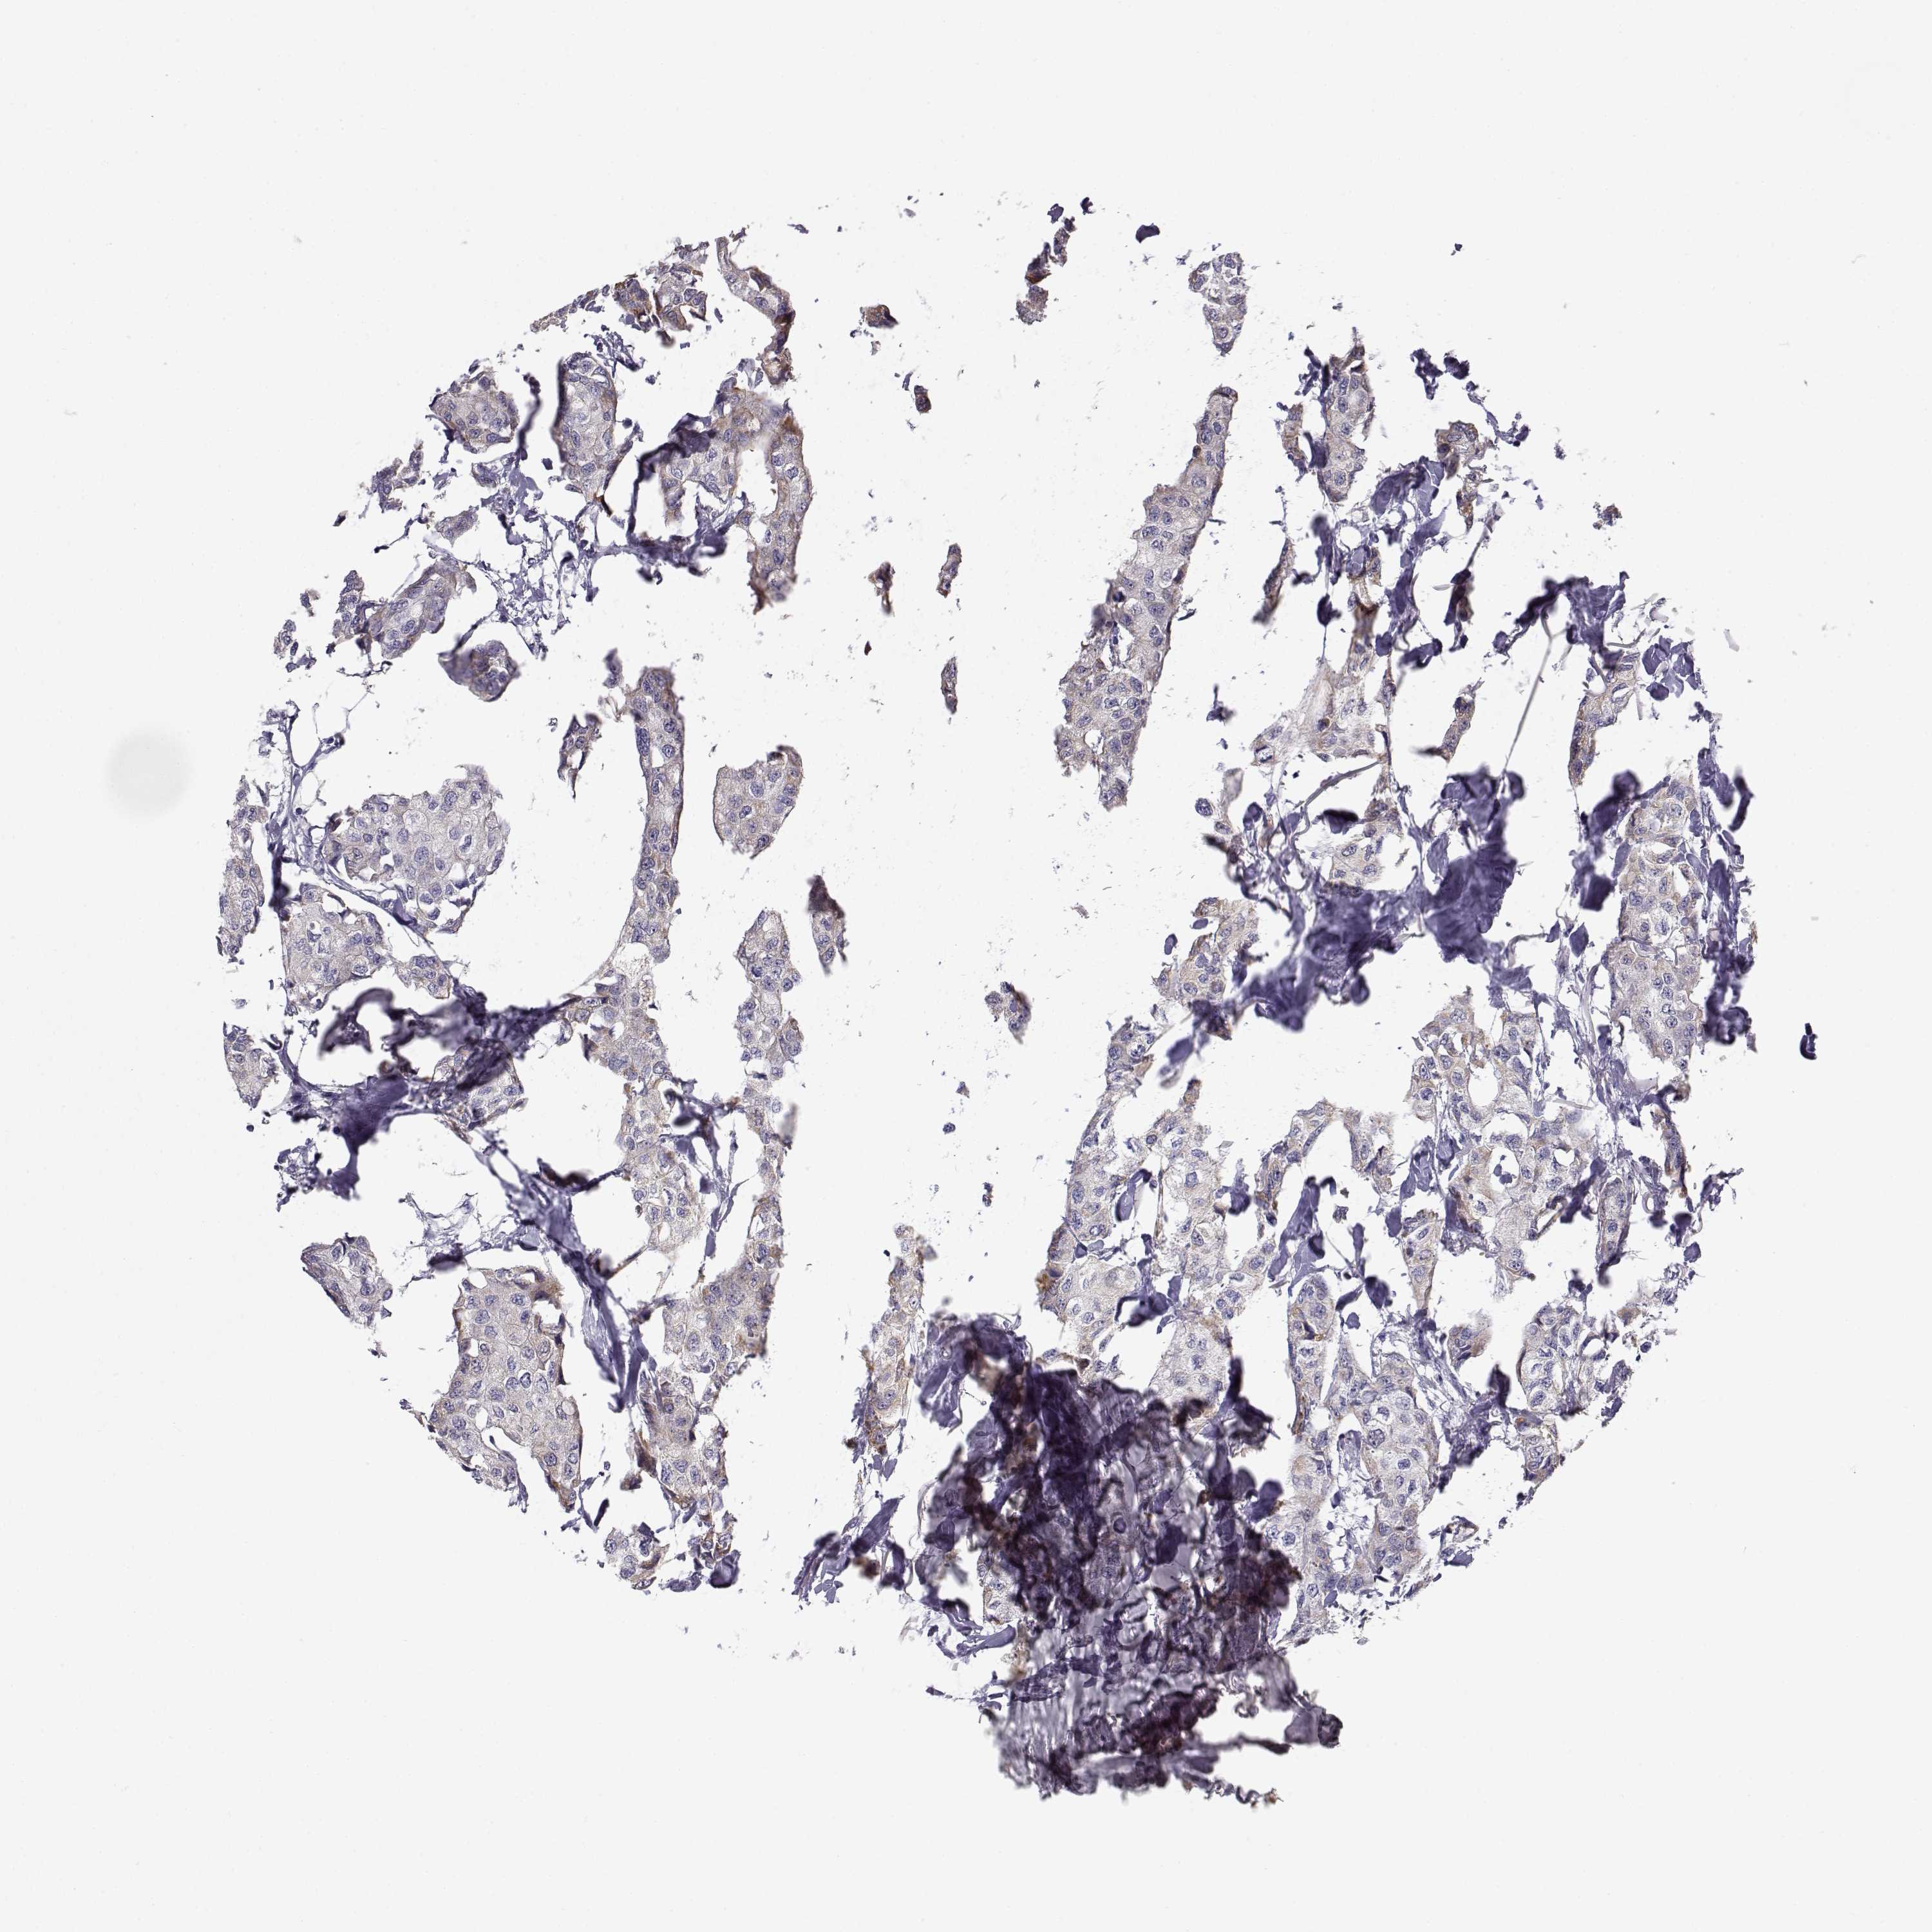

BRCA TCGA BRCA VALIDATION PROTEIN EXPRESSION

Breast cancer

Human cancer